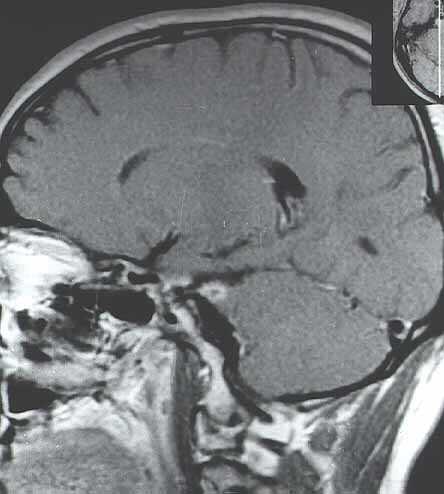

Fig. 2.Imagen sagital con las mismas características que las de la Fig. 1.

Fig. 1. Imagen coronal de MRI con contraste ponderada en T1 en la que se observa una captación nodular del trigémino derecho en su zona de salida de la protuberancia, sugestiva de schwannoma trigeminal.